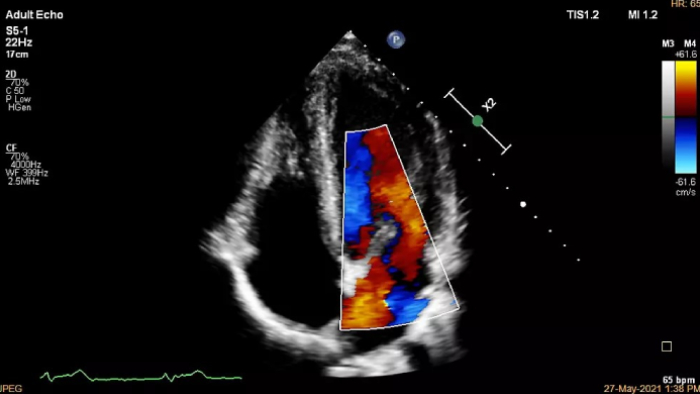

Increase diagnosis confidence and clinical efficiency through superior image quality, advanced quantification tool and automation technology.